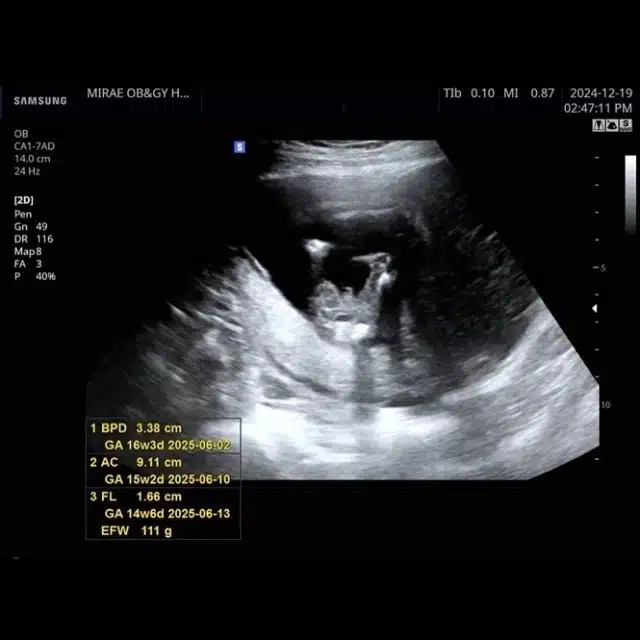

L’actrice Jeon Sung Cho, bien connue pour ses rôles marquants à la télévision coréenne, a récemment fait des révélations sur sa vie personnelle via son compte personnel. Elle a partagé avec ses followers que 2024 a été une année de hauts et de bas, marquée notamment par la perte d’une grossesse il y a un an. Dans un geste de transparence rare, elle a également annoncé qu’elle attendait à nouveau un enfant, une nouvelle qu’elle a découverte lors d’un voyage en Australie.

L’annonce de sa grossesse a été faite d’une manière assez unique. Lors d’un séjour à Sydney, elle a appris qu’elle était enceinte. Emue par cette découverte, elle a choisi « Sydney » comme surnom affectif pour son futur enfant, témoignant de l’importance de ce lieu dans son parcours personnel récent.